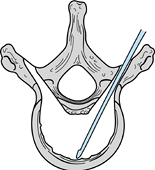

Locate the pedicle by plain radiographs

along the lateral margin of the pars interarticularis (Fig. 161.17).

Figure 161.17. Entrance to the pedicle posteriorly. -